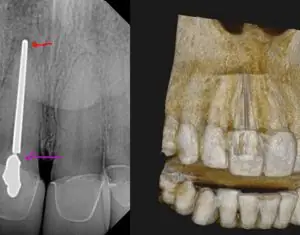

A Short Case Study: A Large Overextended Silver Point with Periapical Pathology 2020-07-28 A patient came in with discomfort on tooth No. 8. He had a draining sinus tract with slight swelling (figure 1, left). He did not